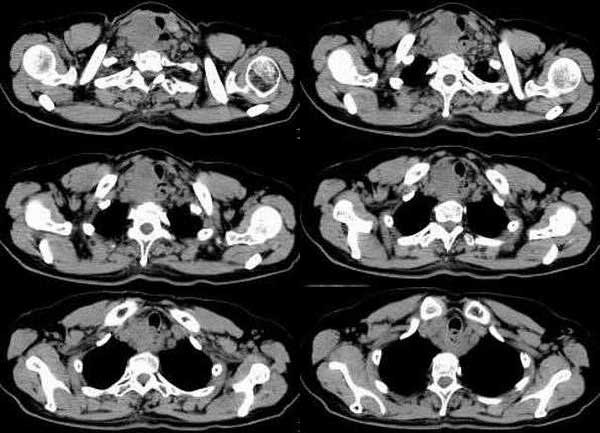

CT01029:[讨论]将在明天下午(2.24)出病理结果! ...

CT01029:[讨论]将在明天下午(2.24)出病理结果!

女,61岁,吞咽困难(包括开水)已久。

考虑食道癌伴淋巴结转移 [emb6]

食道中上段癌伴锁骨上窝淋巴结转移!!!

食管癌并淋巴转移。注意一点是此类患者不要做食道钡透,要用碘类造影剂。